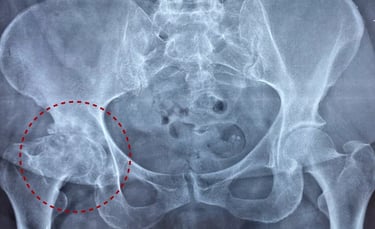

La osteoartritis se caracteriza por el "desgaste" de las articulaciones del cuerpo debido al envejecimiento normal, pero puede acelerarse y aparecer antes en la vida debido al uso excesivo intenso y repetitivo de estas articulaciones. Factores como los genes, el peso y los antecedentes de lesiones o accidentes de las articulaciones también pueden provocar osteoartritis. Afecta con mayor frecuencia a las caderas y las rodillas, pero la columna, las manos, las muñecas y los tobillos también suelen ser áreas problemáticas. El desgaste provoca el adelgazamiento de los discos o cartílagos entre las superficies óseas de las articulaciones y la fricción posterior. El dolor, la inflamación y los depósitos óseos (osteofitos) resultantes de esto hacen que el tejido blando circundante se acorte y la persona reduzca el uso de la articulación. Esta movilidad reducida priva a la articulación de una lubricación, drenaje y nutrición adecuados y los músculos alrededor del área pueden inhibirse y debilitarse.

Mantenga una actitud positiva: recuerde que las investigaciones muestran que un gran número de personas con artritis que se muestran en radiografías o resonancias magnéticas no presentan ningún síntoma. ¡Vos podrías ser uno de ellos!